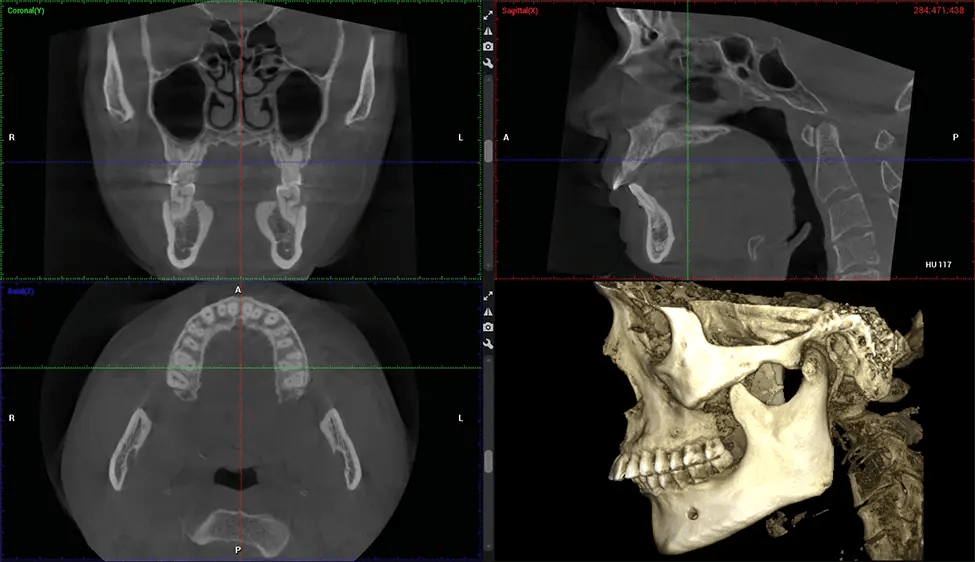

Cone Beam Computed Tomography (CBCT) is an advanced imaging technique used in dentistry and maxillofacial surgery to obtain detailed 3D images of the oral and maxillofacial structures. At Dr G Dental Studio, our CBCT scanners utilize a cone-shaped X-ray beam and a specialized detector to capture images from different angles. A computer then combines these images to create a 3D representation of the patient’s oral anatomy.

This 3D scan, called cone beam computed tomography, gives your dentist a more complete image of your oral anatomy and disease processes than a traditional X-ray. Unlike conventional X-rays, which capture a 2D image of your mouth from various angles, a 3D scan takes multiple digital X-rays for one image. It provides a complete view of your jaw, teeth, nerves, and soft tissues. This enhanced view allows dentists to detect minor issues not visible in traditional 2D scans, such as impacted wisdom teeth or bone fractures in the sinus cavity.

There are many benefits to using CBCT technology, especially compared to the traditional 2D X-ray format. One of the most significant advantages of CBCT scans is that they provide much more information than traditional X-rays. A scan lets your dentist see images from all angles of your jaw and mouth, including your sinuses, nasal cavity, cheekbones, and other surrounding areas. This added information helps your dentist craft a comprehensive treatment plan that addresses all aspects of your oral health.

Another significant benefit is that 3D imaging provides more precise images of your bone structure. These images are more detailed, providing you with a more accurate diagnosis. An accurate diagnosis means better treatment for you.

The patient is first positioned in the CBCT scanner, which typically consists of a rotating arm that houses the X-ray source and a detector. The patient’s head is immobilized to ensure accurate image capture. The X-ray source and detector rotate around the patient’s head, capturing various X-ray images from multiple angles. As the X-ray source rotates, it emits the cone-shaped X-ray beam towards the detector. The detector captures the X-ray images, which are then processed by the CBCT software.

After the scanning process, the captured X-ray images are processed by the CBCT software, which applies algorithms to reconstruct a detailed 3D image of the scanned area. The software compiles these individual X-ray images and creates a digital 3D representation of the patient’s anatomy. The reconstructed 3D CBCT image can be viewed and analyzed by the dentist or radiologist. This image can be manipulated, rotated, and zoomed in or out to examine specific structures and evaluate the patient’s condition.